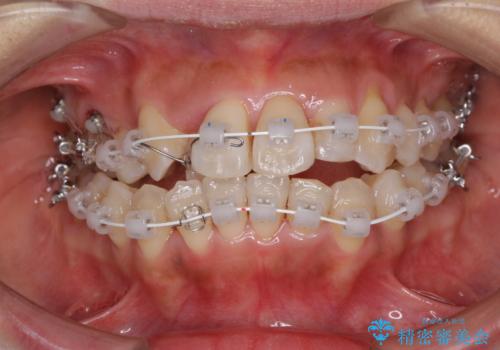

- 審美装置

上顎骨を急速拡大装置により拡大し、ワイヤー装置による抜歯矯正治療を行うこととしました。

治療途中、長期間海外旅行をされたり、帰国後には遠方へ転居されたりと、治療期間が伸びましたが、2年強で治療を終えることができました。